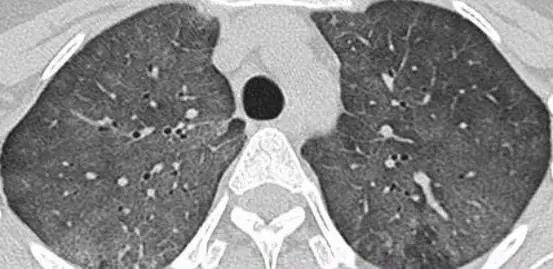

外源性过敏性肺泡炎肺部影像

为寻求进一步诊治,张先生来到了我院。呼吸与危重症医学科宋刚主任详细审阅了张先生的肺部CT片和相关检验报告,并询问了接触史,最终确诊张先生患有外源性过敏性肺泡炎

外源性过敏性肺泡炎(HP),也称过敏性肺炎,是一种由反复吸入某些具有抗原性的有机粉尘所引起的过敏性肺部炎症。过敏性肺炎比较明显的特征就是间质性肺炎、肉芽肿、细支气管炎,其症状包括咳嗽、咳痰、呼吸困难、发热、乏力和胸痛等,影像学表现为弥漫性肺部改变,以中上肺叶为主。